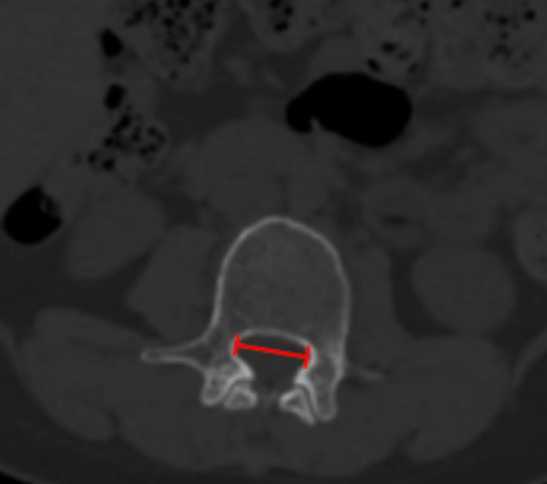

Interpedicular Distance

CT Scan